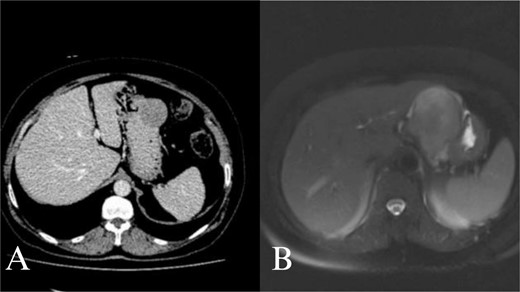

A 70-year-old female was referred to our hospital because of a 6-month history of abdominal discomfort and epigastralgia. Admission vitals, physical exam, routine blood tests, and tumor markers showed normal results. Upper GI endoscopy revealed one protruding lesion 8 cm in size at the lesser curvature of the gastric body. Fine needle aspiration showed chronic inflammation without malignancy. Computed tomography (CT) of the upper abdomen showed a mass originating from the greater curvature of the stomach (Fig. 1A). With suspected GIST, we proceeded with surgery. At laparotomy, an 8 × 7 × 7 cm mass was found at the greater curvature and resected en-bloc with gastric wedge resection. Microscopically, the tumor consisted of spindle cells, positive for S-100 protein and vimentin, while negative for CD 117, CD 34, β-catenin, SMA, synaptophysin, chromogranin, and desmin, consistent with schwannoma (Fig. 2A and B). Postoperative recovery was smooth, and the patient was discharged on Day 5. At 2 years, the patient remains healthy and recurrence-free.

Abdominal CT and MRI images. Contrast enhanced axial tomography revealed a hipodens mass with smooth boundary located at the greater curvature of the stomach. Axial T1 weighted MRI revealed a hypointense, moderate contrast enhancing mass with smooth boundary located at the gastric antrum.

A 66-year-old female with a history of abdominal discomfort, epigastralgia, and anemia for 10 months was admitted. The results of admission showed good vital status and general condition except for a low level of hemoglobin at 7.0 g/dL and hematocrit at 23.1%. Upper GI endoscopy showed a submucosal mass at the greater curvature of the antrum. Biopsy cytology demonstrated spindle cell morphology and thus suspected GIST. CT and magnetic resonance imaging (MRI) revealed the mass at the gastric antrum with smooth-bounded margins without lymphadenopathy (Fig. 2B). Laparotomy showed a mass measuring 6 × 6 × 7 cm. En-bloc excision of the mass had been done with subtotal gastrectomy and Roux-en-Y reconstruction. This was histologically proven through positive S-100 and vimentin markers that are negative for CD 117, CD 34, and other markers and confirmative of schwannoma. She did well post-operatively and was discharged on Day 7. She remains well at 18 months follow-up with no recurrence.

The main differential diagnosis for GS is a GIST [8]. It is always very difficult to discriminate a GS from a GIST, so schwannomas are often misdiagnosed as GISTs on radiological examinations [2, 12]. It is necessary to discriminate GS from other gastric submucosal tumors, especially from GISTs. Although similar small GISTs and GS may have findings on imaging in common, GS more frequently exhibit exophytic or mixed growth patterns, a homogeneous enhancement pattern, perilesional lymph nodes, and slower growth compared to GISTs [13]. GS are usually well-defined, rounded mural masses with homogeneous attenuation and tend to lack cystic change and hemorrhage on CT scan. Typically, GS are sharply demarcated, strongly enhancing tumors, having low to medium signal intensity on T1-weighted images and high signal intensity on T2-weighted images.